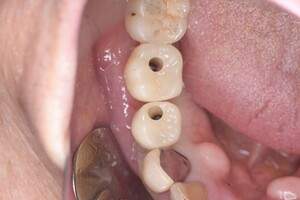

口腔内写真-1

口腔内写真-2

- Befor

- After

| 年齢 | 60代・男性 |

|---|---|

| 主訴 | 左上5番6番 |

| 治療内容 | インプラント埋入 |

| 治療費 | インプラント埋入料 825,000円 ソケットリフト(骨造成) 220,000円 サージカルガイド 66,000円 2次OPE 44,000円 静脈内鎮静麻酔 77,000円 合計 1,232,000円 (2024年1月現在) |

| 治療期間 | 10ヶ月 |

| リスク・副作用 | リスク・副作用 |

| 治療方針 | 左上5番6番目の歯根破折の為抜歯を行いました。その後インプラント埋入を行いました。 |

| 特記事項 | インプラントは人工物なので虫歯になることはありませんが、歯周病(インプラント周囲炎)にはなります。 インプラントを長持ちさせるには、毎日の歯磨きと合わせて、3〜6ヶ月ごとの定期検診でのクリーニングが大切です。 |

| 担当者所見 | 歯を失ったまま放置してしまうと、周囲の歯に負担がかかるため、お口の中全体のバランスが崩れます。 インプラントは、骨に人工の歯根を埋め、被せ物を被せる治療法です。 外科的な手術が必要ですが、健康な歯を削ることなく、天然の歯と同じようにかめるようになります。 |